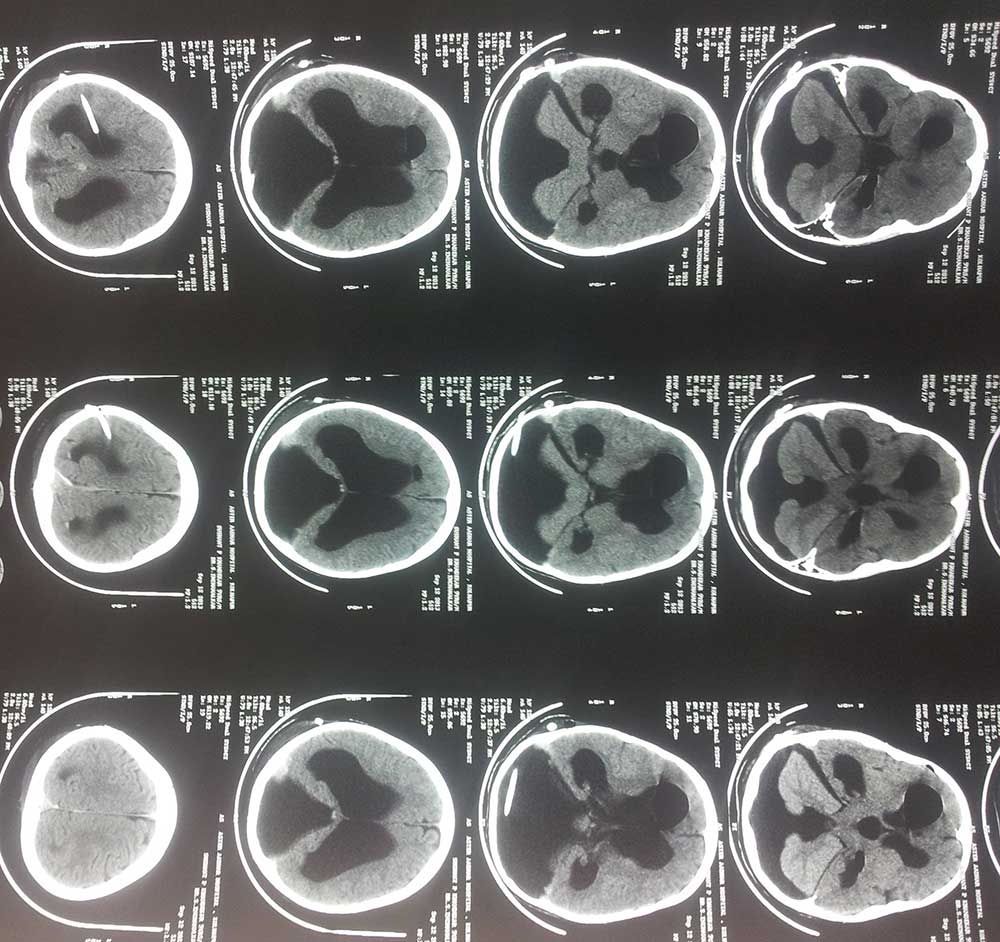

post op ct

• post op ct